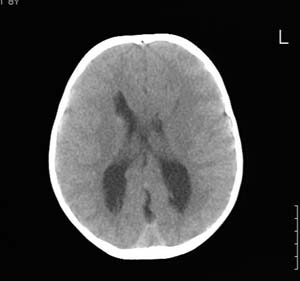

以下是引用wxy7406在2006-12-5 21:02:00的发言:[br]后颅窝囊性低密度灶,双侧小脑半球缩小,蚓部几乎缺失,考虑dandy-walker畸形,建议mri明确。

以下是引用阿圣在2006-12-5 20:55:00的发言:[br]后颅窝囊性低密度灶,双侧小脑半球缩小,蚓部几乎缺失,考虑dandy-walker畸形,建议mri明确